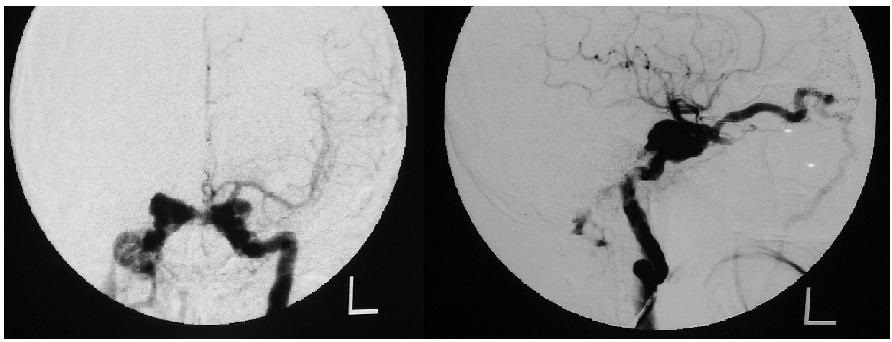

Przyporządkuj najczęstsze objawy do patologii przedstawionej na angiogramach lewej tętnicy szyjnej wewnętrznej:

1) wytrzeszcz tętniący; 4) sztywność karku;

2) ból zlokalizowany za gałkami ocznymi; 5) ophtamoplegia.

3) silny ból głowy;

Prawidłowa odpowiedź to: